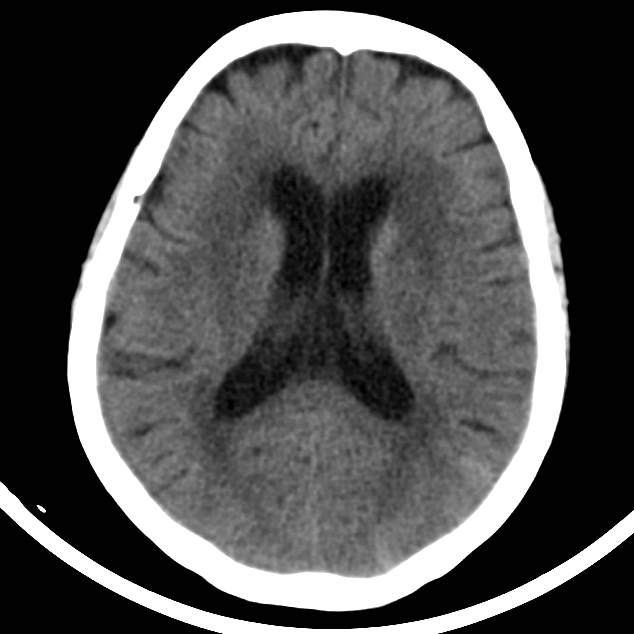

一位76岁的老人家,说最近10天一直脖子疼和腰疼,休息后也无明显缓解。人年龄大了,这个脖子和腰部啊,在气候交替的季节,有点疼痛似乎也是司空见惯的事情,可能受凉了呗。近10天来,患者也在医院几个科室之间辗转,后来拍了一张脑CT,颅内隐约在一个脑沟内有点淡淡的、若有若无的高密度影,不仔细看,都看不到的那种若隐若现~~~,你说是颅内出血或者蛛网膜下腔出血吧,老人家也没有说过头痛啊,这主诉和查体似乎也不太支持出血的诊断~~~;你说是皮层静脉血栓吧,后续的窦和深静脉也没有看到高密度啊,也不太支持血栓~~~,这无缘无故的一个脑沟的高密度似乎也不能空穴来风吧?